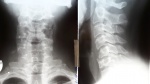

Мужчина, 33 года. Как думаете, доктора, что с С6, травматическое, передняя грыжа?высота снижена в сравнении с рядом стоящими позвонками. В анамнезе травма черепа

РГ ШОП 2 пр. ID:69210

Похоже раньше был компресс.перелом С6, сейчас посттравматические изменения в виде клиновидной деформации С6, обызвествления в проекции м/п диска С5-С6.

+1! Грыжа сомнительна.

"В анамнезе травма черепа". Хотелось бы знать что за травма, её механизм, как давно была (год-два назад, или неделя не прошла)? Сам бы заключил консолидированные компрессионные переломы С5-6 с клиновидной деформацией 1 ст.

+1(обызвествление связки заменила бы на компенсаторные костные разрастания. Они с боку есть.)

только узнал. травма 5 лет назад. упал вертикально на голову. перелом черепа. Про ШОП  пациент не знал ничего.